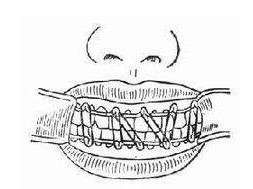

闭合式复位和固定

复位的方法有:(1)手法复位 对于早期简单的线形骨折,骨折段比较松动,局麻下手法即可复位。(2)牵引复位 长见颌间牵引复位,即在上下颌牙列上结扎牙弓夹板,然后用橡皮圈进行牵引,以咬合为依据,使移位的骨折段回复正常位置。如髁突骨折伴有下颌后缩前牙开合的患者,可用此方法进行复位。

2. 固定的方法:(1)单颌固定 即在发生骨折的下颌骨上进行牙间或骨间固定,适用于无明显移位的线形骨折。目前最常用的固定的方法为单颌牙弓夹板固定。 (2)颌间固定(牵引) 颌间固定是在上下颌牙弓上结扎牙弓夹板,然后用橡皮圈将上下颌骨固定在一起,利用上颌完好的牙弓为依据,以恢复咬合关系,从而恢复下颌骨的连续性。